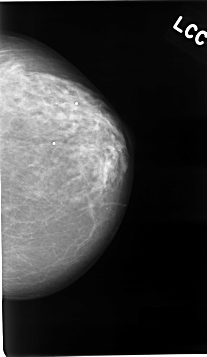

C_0041_1.LEFT_CC

LEFT_CC LINES 4632 PIXELS_PER_LINE 2680 BITS_PER_PIXEL 12 RESOLUTION 50 NON_OVERLAY